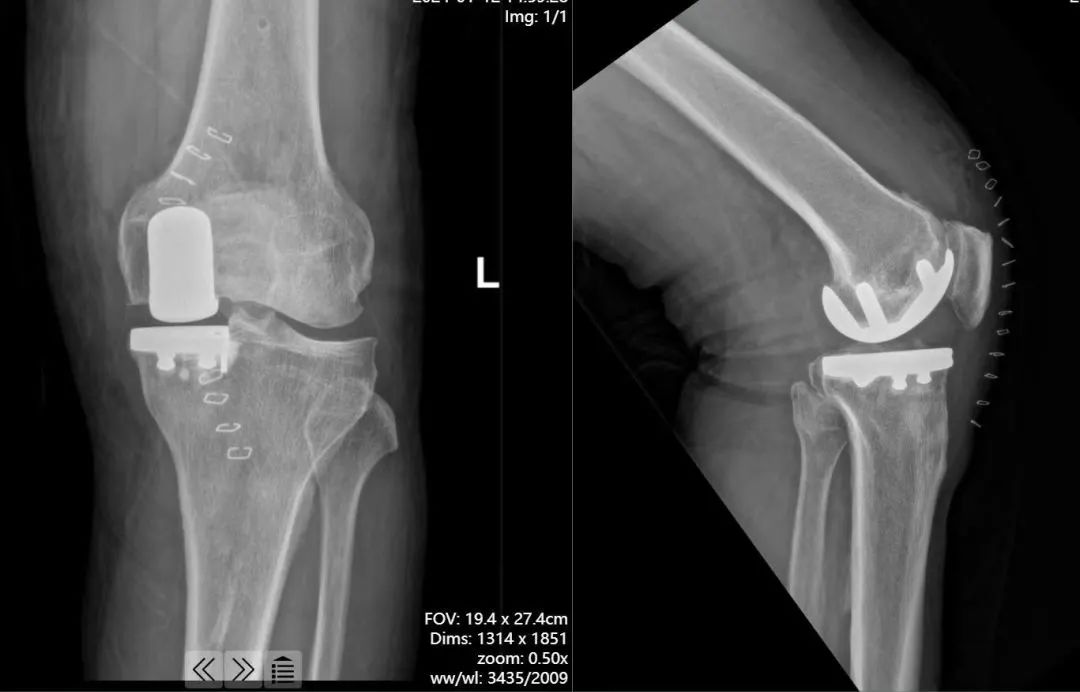

儿子就带着父亲,来到了河北医科大学第一医院膝关节二科,门诊秦永辉医生为他安排 X 线检查。结果提示膝关节内侧,已经到了骨头磨骨头的阶段,如果继续保守治疗,不会有很好的效果,建议手术进行干预。

于晓光主任为患者进行了仔细的查体和一系列术前检查,确定患者前内侧骨关节炎的病变,仅局限在一个间室,可以用微创的单髁置换手术解决。家属经考虑后选择了更加智能化、个体化的治疗方式机器人辅助膝关节单髁置换手术